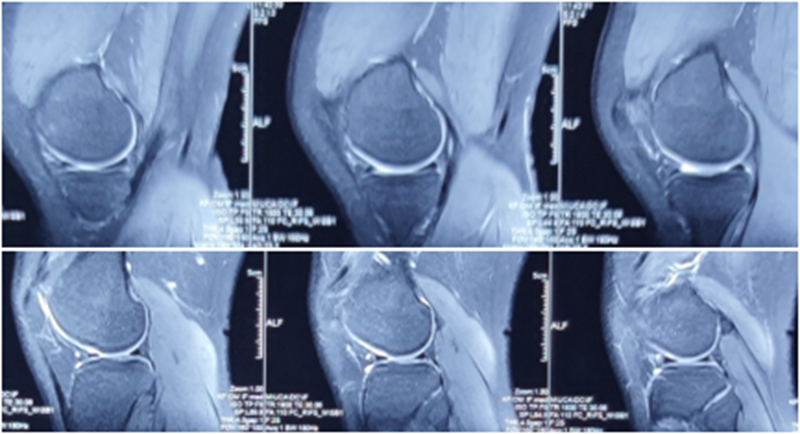

术前MRI

镜下显示ACL残束